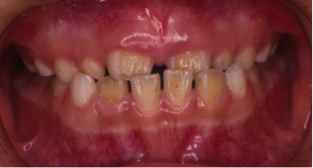

開咬(かいこう)

24歳/女性

悩み:前歯が噛めない

奥歯は噛み合っていても上と下の歯に隙間が空いてしまう状態

治療期間:約3年

治療前

前歯で噛む事が出来ないとの悩みから来院された患者様で、開咬症例ではあるのですが突出傾向があったため、小臼歯4本抜歯をする治療方針で約三年ほどかかって治療いたしました。治療後にはきちんとものが噛めるようになり、約三年間の頑張りが報われましたと喜んで頂けました。